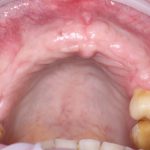

Откроем область операции и посмотрим, что там:

Вроде как, всё неплохо. Наверное, можно поставить имплантаты?

ну, или как-то так: